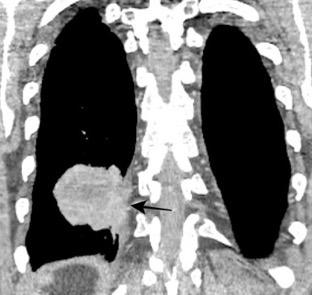

100. TUMOR FANTASMA

102. TUMOR FANTASMA. HEMATOCELE

En relación con trasudados tabicados. Insuficiencia cardiaca

Hipoalbuminemia

Cirrosis / Fallo renal.

Operado aneurisma (prótesis). Líquido tabicado en cisuras

Derrame pleural “encapsulado”

“Tumor fantasma”

Asociado a fallo cardiaco. ( “Pleuritis adhesiva”). Buch KP. Chest. 2000